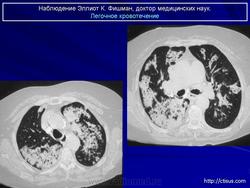

Продолжение.